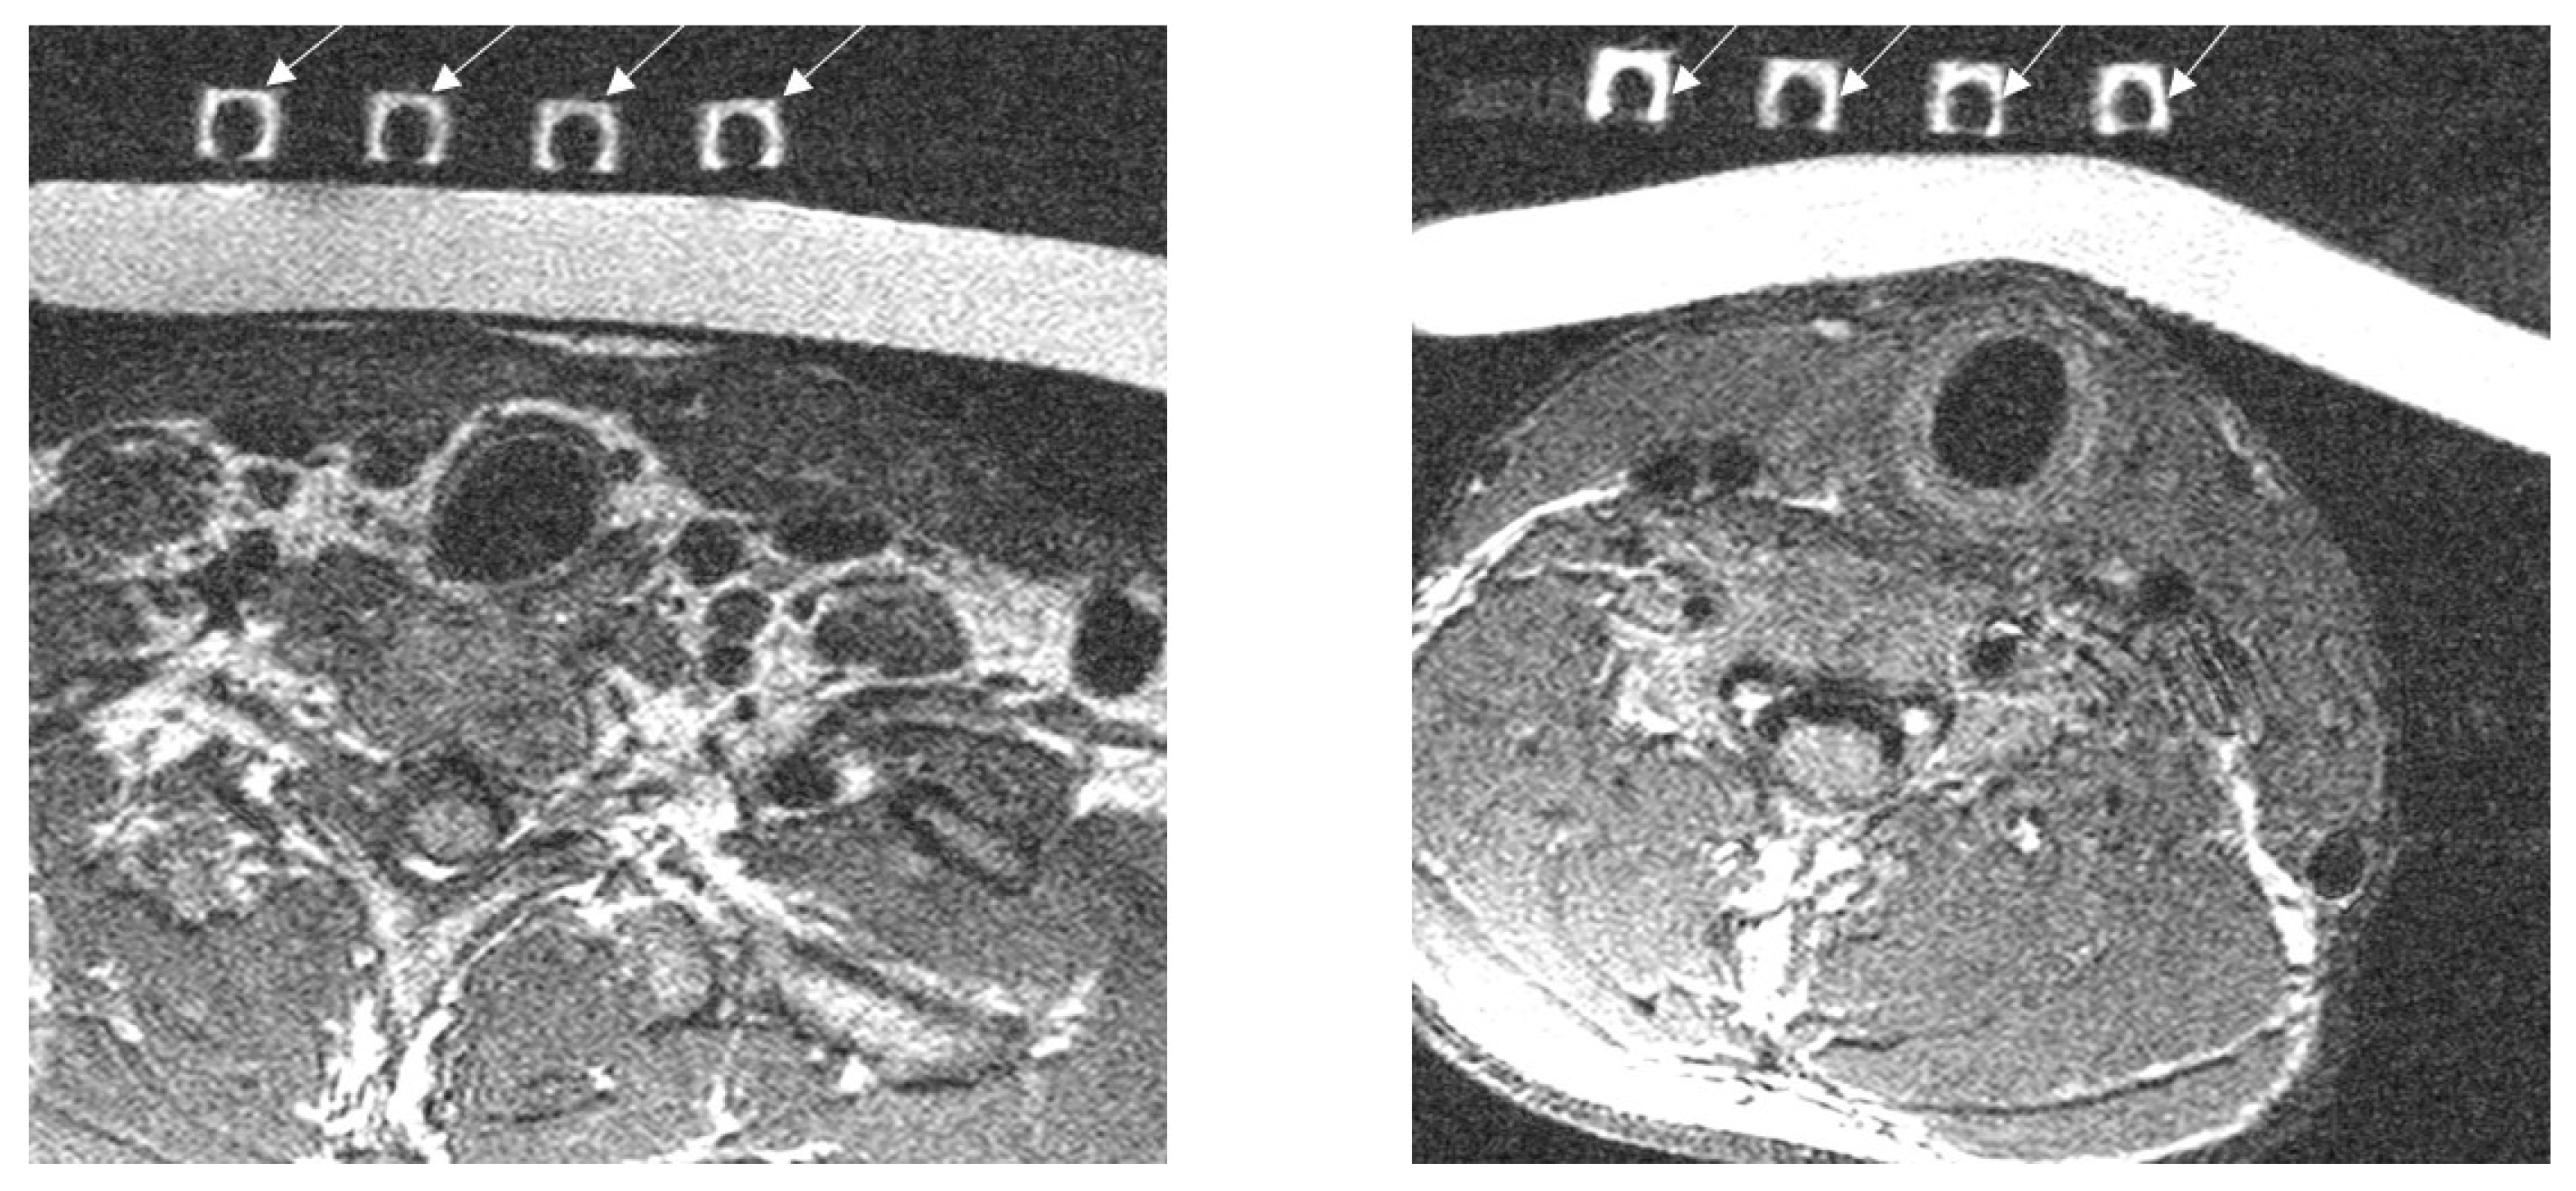

2.5. Experimental Imaging of the Human Neck

3.3. Imaging of the Neck